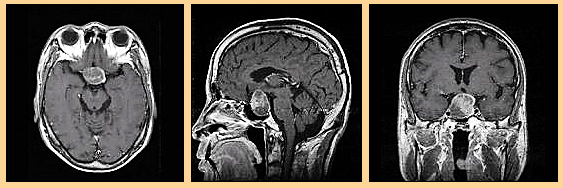

이번 성공사례는 뇌하수체 선종 (D35.2) 을 진단받고 암보험금을 전액 지급 받은 사례입니다.

이번 사례의 피보험자 OOO님도 조직학적으로는 암이 아니며, 질병분류번호 또한 D35.2로 양성종양 진단을 받았습니다. 그렇지만 결론적으로는 보험사로부터 암보험금 지급이 적정하다는 결론을 얻었고 그에 따른 보험금을 지급 받았습니다.

뇌하수체 선종은 말그대로 뇌의 기저부에 있는 뇌하수체에 발생한 선종, 즉 종양을 말합니다. 많은 뇌종양의 종류중 위치적인 이유에서 불린다고 생각하면 됩니다.

흔히 말하는 암은 이 종양이 '악성'일때를 말하는것으로, 조직검사 결과를 바탕으로 합니다. 그런데 이 뇌하수체 선종은 말그대로 선종일 뿐으로 조직학적으로는 '악성'이 아닌것입니다. 그래서 [위치적인 '뇌하수체'+ 종양의 형태 '선종']으로 뇌하수체 선종이라 합니다.

진단서에서와 같이 뇌하수체 선종 진단하에 경접형동 종양제거술을 하셨습니다. 뇌하수체 선종을 암보험금으로 인정받기위한 분쟁도 있지만, 이번 사례는 그외에 2011년 1월 진단받은건으로 청구권 소멸시효에 대한 분쟁도 추가로 있었기 때문에 많은양의 손해사정 보고서 작성이 이루어졌습니다.

진단서, 보험증권, MRI기록등 간단한 서류만으로 1차적으로 상담이 가능합니다.